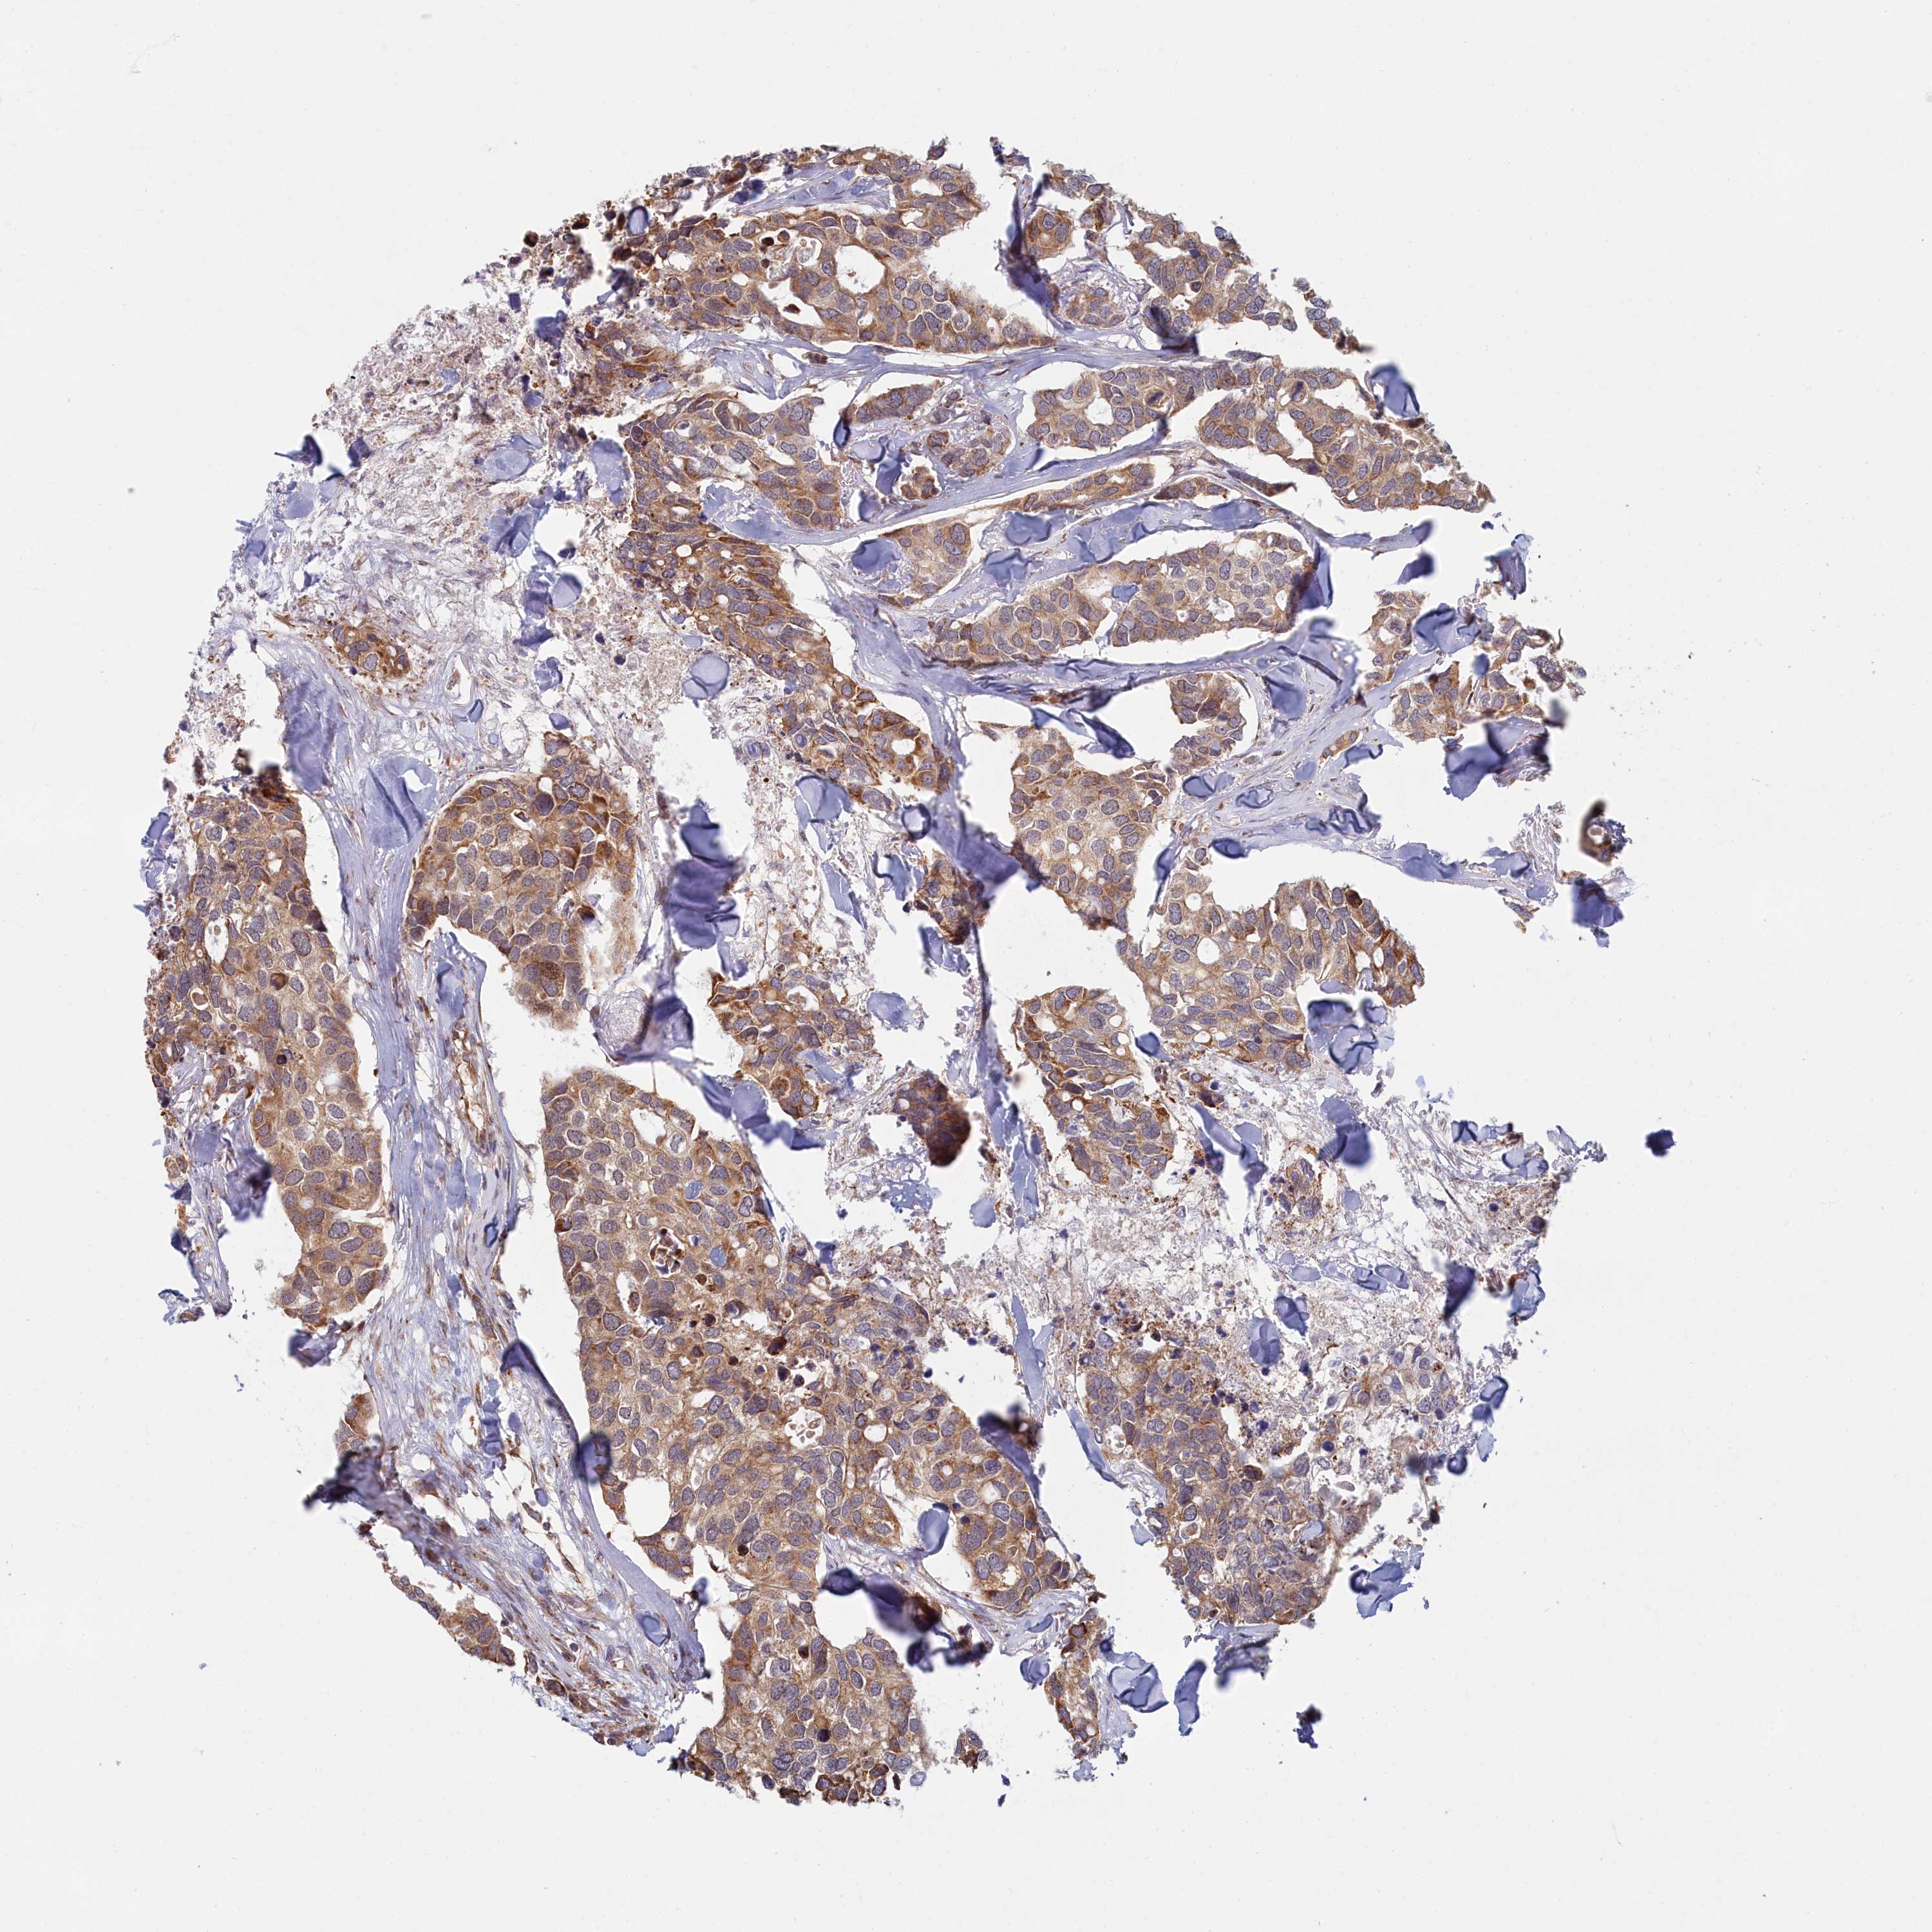

CANCER BREAST CANCER Show tissue menu

BRCA TCGA BRCA VALIDATION PROTEIN EXPRESSION

Breast cancer

Human cancer

Breast invasive carcinoma